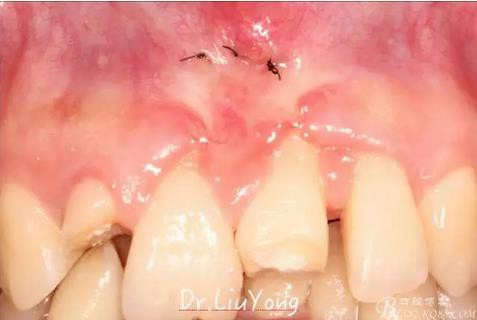

上唇系帶手術(shù)后一周拆線,如上圖

系帶手術(shù)后兩周,進(jìn)行上頜前牙唇側(cè)的牙齦退縮的手術(shù)治療,由于局部附著齦缺如及牙齦厚度不足,因此同期進(jìn)行上皮下結(jié)締組織移植,解決附著齦及牙齦厚度不足的問(wèn)題。